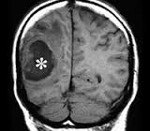

Точность диагностирования абсцесса головного мозга с помощью КТ головного мозга зависит от стадии формирования абсцесса. На ранних стадиях заболевания диагностика затруднена. На этапе раннего энцефалита (1-3 сутки) КТ определяет зону сниженной плотности неправильной формы. Введенное контрастное вещество накапливается неравномерно, преимущественно периферических отделах очага, реже в центре. На более поздних этапах энцефалита контуры очага приобретают ровные округлые очертания. Контрастное вещество распределяется равномерно, по всей периферии очага; плотность центральной зоны очага при этом не меняется. Однако на повторной КТ (через 30-40 минут) определяется диффузия контраста в центр капсулы, а также наличие его и в периферической зоне, что не характерно для злокачественных новообразований.

Инкапсулированный абсцесс мозга на КТ имеет вид округлого объемного образования с четкими ровными контурами повышенной плотности (фиброзная капсула). В центре капсулы зона пониженной плотности (гной), по периферии видна зона отека. Введенное контрастное вещество накапливается в виде кольца (по контуру фиброзной капсулы) с небольшой прилежащей зоной глиоза. На повторной КТ (через 30-40 минут) контрастное вещество не определяется.

МРТ головного мозга — более точный метод диагностирования абсцесса головного мозга. При проведении МРТ на первых стадиях формирования абсцесса мозга (1-9 сутки) энцефалитический очаг выглядит: на Т1-взвешенных изображениях — гипоинтенсивным, на Т2-взвешенных изображениях — гиперинтенсивным. МРТ на поздней (капсулированной) стадии абсцесса головного мозга: на Т1-взвешенных изображениях абсцесс выглядит, как зона пониженного сигнала в центре и на периферии (в зоне отека), а по контуру капсулы сигнал гиперинтенсивный. На Т2-взвешенных изображениях центр абсцесса изо- или гипоинтенсивный, в периферической зоне (зоне отека) гиперинтенсивный. Контур капсулы четко очерчен.